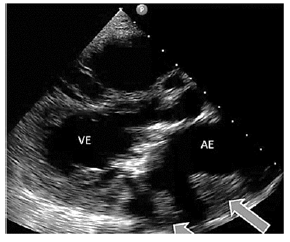

Um paciente de 52 anos de idade, HIV positivo, em ritmo sinusal, apresentou quadro de síndrome coronariana aguda. Ao realizar cateterismo, não havia sinais de doença aterosclerótica. O paciente foi submetido a tromboaspiração. Após o procedimento, foi realizado um ecocardiograma à beira do leito, demonstrado na imagem.

Assinale a alternativa que indica a provável valvopatia associada e o corte ecocardiográfico, respectivamente.